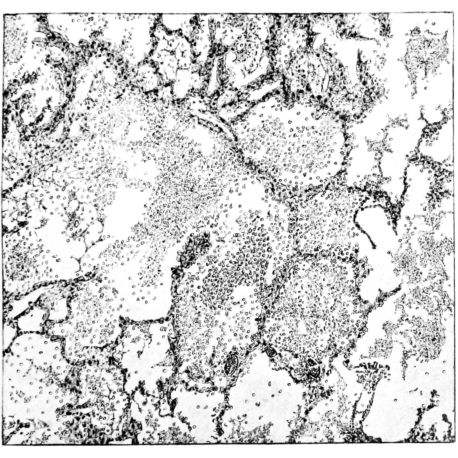

FIG. III. AUTOPSY NO. 90. DRAWING FROM A LESION OF THE TRACHEA (SOMEWHAT OLDER THAN THAT ILLUSTRATED IN FIGURE II). THE MUCOSA IS ENTIRELY LACKING. CONGESTION AND EDEMA ARE THE STRIKING FEATURES IN THE SUBMUCOSA. THE NECROTIZING PROCESS HAS EXTENDED INTO THE MUCUS GLANDS. THIS IS SHOWN IN THE LOWER PICTURE.

The changes are less marked, perhaps, in the trachea than in its finer ramifications. The mucosa is constantly more or less destroyed and large areas, usually focal, are entirely devoid of their epithelial covering. This is replaced by a sparse exudate, composed largely of red blood cells, mucus, a small amount of fibrin, and nuclear fragments (Fig. II). It may dip into the submucosa for a short distance, but usually these indentures are associated with the ducts of the mucous glands into which the inflammatory reaction extends. A more striking feature than the exudate, however, is the edema and the congestion of the submucosa. The loose areolar tissue of the submucosa is spread widely apart, and throughout it distended blood vessels are very conspicuous. Occasionally such a vessel is broken and actual hemorrhage appears in the submucosa. Occasionally, too, the inflammation extends down the duct to the mucous gland itself, and here, also, aplastic inflammatory reaction is evident, inasmuch as the acini now stain intensely red with the cells undifferentiated from each other and specked here and there by broken remains of the dead nuclei (Fig. III). After the disease has continued for a short period, even at the end of five or six days, some regeneration of the epithelial lining may be seen (3) (Fig. IV). But despite this, the acute picture persists, and there goes on, side by side, an attempted repair characterized by epithelial regeneration and the same evidence of acute change. Since the lesion is essentially a superficial one, scars or contractures of any extent are not encountered in the trachea, even in examples of the disease that have ended fatally only after many weeks.[4]